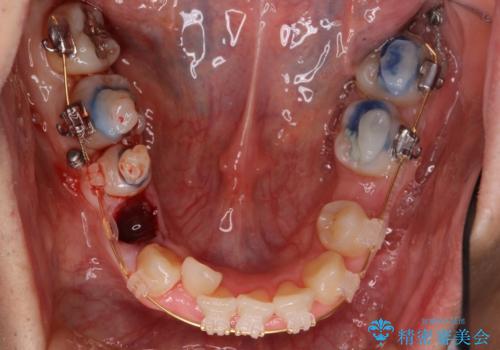

- 矯正装置

- 審美装置

- 治療期間

- 6年3ヶ月

- 治療回数

- 30回以上

かみしめもあり、骨も固く、歯根も長いためなかなか歯が動かず、患者様も治療する側も忍耐を要する長期戦となりました。